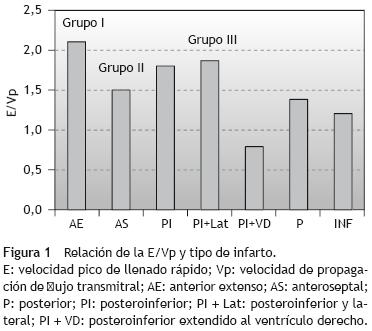

Resultados: Se dividió a los pacientes en 3 grupos: grupo I: restrictivo (TD < 140 ms, E/Vp > 2, E/A > 2, E/E' > 15; grupo II: presiones de llenado elevado (TD > 140 ms, E/Vp > 2, E/A 1,2, E/ E' < 15), y grupo III: presiones de llenado normal (TD > 140 ms, E/Vp < 2, E/A < 1, E/E' < 15). La E/Vp mostró una mejor correlación en el grupo con llenado restrictivo y presión de llenado ventricular izquierdo mayor que el grupo con presión de llenado normal a los 90 días (media ± desviación estándar, 2,18 ± 0,90 frente a 1,5 ± 0,35; r = 0,99; p = 0,0001). El volumen diastólico final (VDF) fue similar en los 3 grupos 24 h después del infarto. El VDF varió 90 días después del infarto en quienes se realizó una angioplastia coronaria transluminal percutánea exitosa: grupo I, 142,48 ± 32 frente a 112,48 ± 32 (r = 573; p < 0,0001).

Ecocardiografía Doppler en las primeras 24 h del infarto

Se detectó una correlación positiva entre el tamaño del infarto por pico máximo de creatincinasa (media ± desviación estándar 1.800 ±120) y la relación E/A (r = 0;49; p = 0,0001) y una correlación negativa con el TD (r = 0,52; p = 0,0001). Se dividió a los pacientes en 3 grupos (tabla 1): grupo I: se encontraron todos los infartos de localización anterior extensa; grupo II: localización del infarto anteroseptal y uno posteroinferior y lateral; grupo III: localización del infarto posteroinferior y lateral o extensión al ventrículo derecho (tabla 2). La relación E/A en el grupo I frente a los grupo II y III fue de 1,9 + 0,3 frente 1,0 + 0,35 (r = 0;431; p < 0,001). El TD fue de 149 ± 19 ms frente a 195 ±42 ms (p = 0,01). La E/Vp fue de 2,18 ±0,90 frente 1,2 ±0,2, lo que traduce una presión diastólica final del ventrículo izquierdo de 20,22 ±2,92 frente a 10,92 ±3,38 mmHg (r = 0,99; p < 0,0001) (fig. 1). La E/E' fue de 16.54 ± 2,24 frente 10,79 ±2,18 (r = 0;893; p < 0,001). El VDF del ventrículo izquierdo y el VSF del ventrículo izquierdo fueron similares en los 3 grupos después de 24 h del infarto. El VDF fue de 92,94 ±14,74 y el VSF fue de 53,31 ±19,48. El índice global de contracción fue de 1,79 ±0,21 frente a 1,3 ±0,28 (p = 0,001).